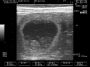

חדשות מרגשות יש הערב. לפני מספר דקות בלבד סיימנו את סריקת האולטרא סאונד של מארם,שהיום עומדת על יום 30 להריון מההרבעה הראשונה. מארם שכבר מראה סימנים חיצוניים היתה ברורה שבעלת שגר גדול, על אף שבסריקה הקודמת ניתן היה לאתר רק 6 עוברים בתוך קפלי המעי, היום ניתן היה לראות בבירור מושלם 9 גורים בריאים, שלמים ובעלי דופק מרגש של 345 פעימות לדקה בממוצע.